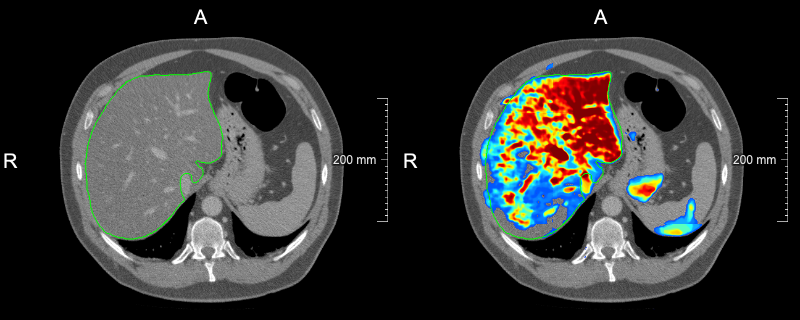

Refer to caption

(a) slice-level uncertainty: 0.0660.0660.066

(b) slice-level uncertainty: 0.0560.0560.056

(c) slice-level uncertainty: 0.0520.0520.052

(d) slice-level uncertainty: 0.0200.0200.020

Figure 2: Examples of slices selected in the first USS iteration with overlaid liver reference segmentation (green contour) and model liver probability output (heatmap): (a)-(c) slices with the biggest slice level uncertainty, (d) slice with the lowest uncertainty among selected ones.

As our strategy relies on the model’s uncertainty to query cases, the confidence calibration of a model can have a substantial impact on which cases are deemed uncertain. Recently, it has been shown that modern deep neural networks do not output well-calibrated probabilities and tend to be overconfident[28]. In our work, we have used MC dropout that improves the calibration quality of models trained with the Dice loss[22]. Exemplary probability maps produced by our model are shown in Fig. 2. We think that investigation of various calibration techniques, e.g., deep ensembles and temperature scaling, in the context of active learning could be an interesting future research direction.